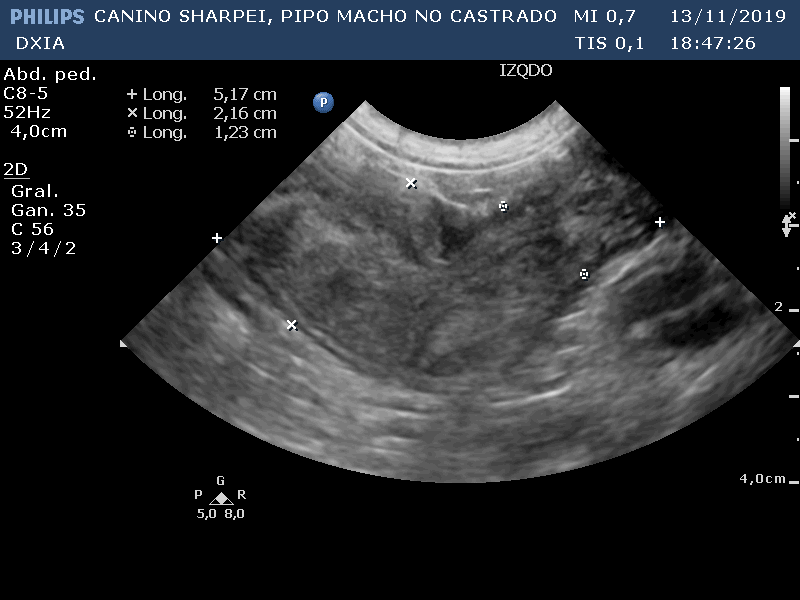

PIPO

Del informe ecográfico de Pipo se destaca la existencia de varias alteraciones:

Comentario imágenes A y B: Comparativa Asas ID normal con asa alterada donde se observa aumento de la pared (engrosamiento) con pérdida de estructura en capas.

Neoformación en ID de la que se realiza PAF ecoguiada.